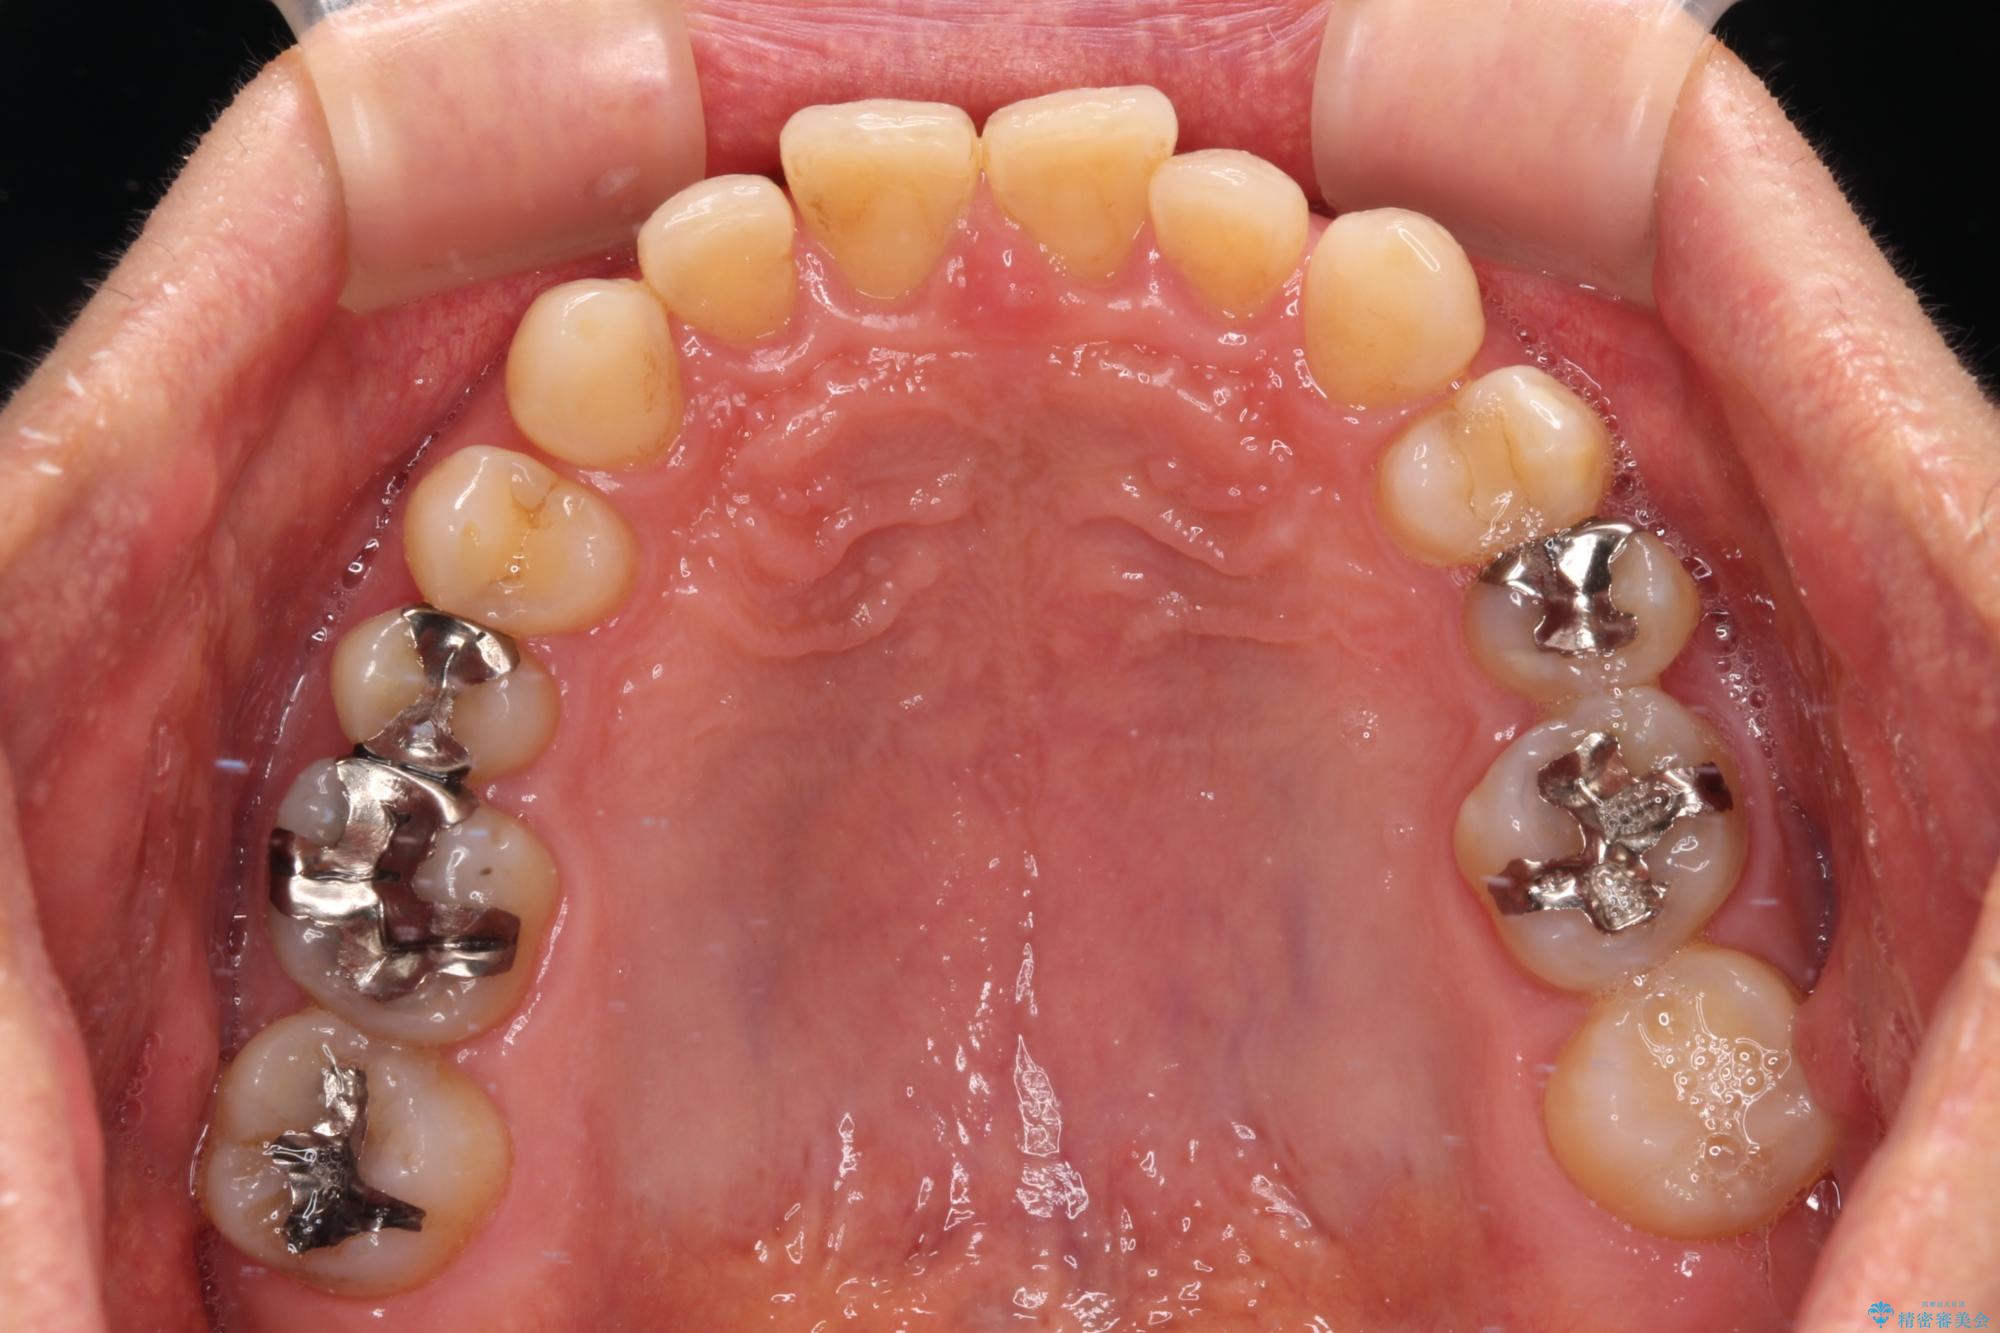

- 前歯のデコボコと隙間の空いた歯列を気にして来院された患者様です。

下顎前歯が隠れるほどのディープバイトにより、強い咬合力と突き上げで上顎歯列に隙間が空いている状態でした。

手前に傾斜している奥歯をワイヤー装置で立ち上がらせ、咬み合わせの高さを挙上することで突き上げを解消し、空隙歯列を改善していくこととしました。